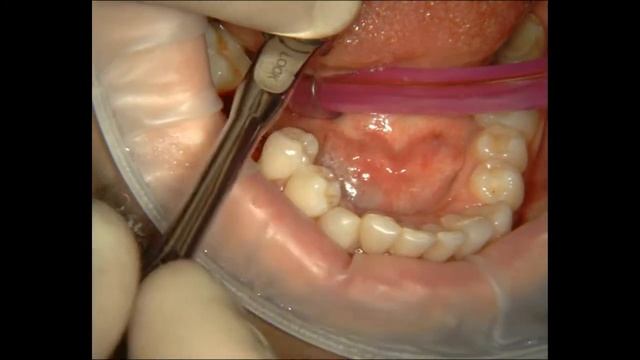

Расщепление альвеолярного гребня в обл.46 и имплантация. смотреть онлайн

02:17

Расщепление альвеолярного гребня в обл.46 и имплантация.

Уход и лечение: медицинские процедуры 643 просмотров